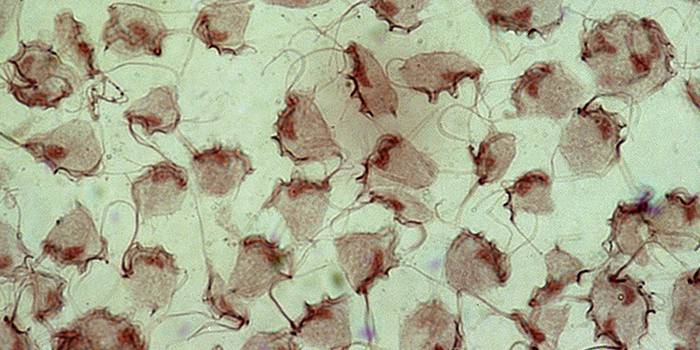

Сущность болезни

Трихомониаз (трихомоноз) представляет собой инфекционное заболевание мочеполовой системы, передаваемое половым путем. Главным возбудителем болезни являются урогенитальные (влагалищные) трихомонады Trichomonas vaginalis. Этот возбудитель причисляется к простейшим одноклеточным микроорганизмам размером порядка 8-20 мкм. Он обладает системой жгутиков, которые обеспечивают высокую степень подвижности.